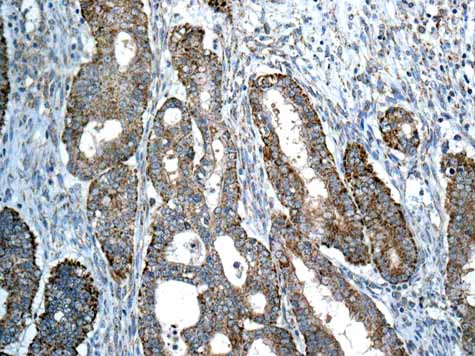

Anti-Map17 antibody [EPR16827]

Rabbit Recombinant Monoclonal Map17 antibody. Suitable for IP, WB and reacts with Human samples. Cited in 1 publication.

Map17 also known as PDZK1IP1 or MCFD2 functions as a membrane-associated protein with a mass of approximately 17 kDa. It localizes primarily in the plasma membrane but can also be found in other cellular compartments. This protein is expressed in various tissues with high levels observed in renal and gastrointestinal tract tissues. Its structural characteristic includes a PDZ-binding motif which suggests interactions with PDZ domain-containing proteins playing a role in facilitating membrane transport processes.

Map17 shows a connection with conditions such as cancer and chronic kidney disease. Research indicates its overexpression in various tumors where it may interact with the oncogene Ras to influence tumor growth and progression. In chronic kidney disease its role in ion transport could contribute to altered renal function with proteins like CFTR also involved in this disease context. Understanding Map17’s involvement in these diseases offers insights into potential therapeutic targets and novel treatment strategies.